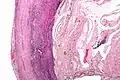

Pathology diagnosis of appendicitis can be made by detecting a neutrophilic infiltrate of the muscularis propria.

Periappendicitis, inflammation of tissues around the appendix, is often found in conjunction with other abdominal pathology.[61]

Classification of acute appendicitis based on gross pathology and light microscopy characteristics[62]

PatternGross pathologyLight microscopyImageClinical significance

Suppurative acute appendicitis May be inapparent.

• Dull mucosa

• Congested surface vessels

• Fibropurulent serosal exudate in late cases

• Dilated appendix

• Neutrophils in mucosa, submucosa and muscularis propria, potentially transmural.

• Extensive inflammation

• Commonly intramural abscesses

• Possibly vascular thrombosis

Can be presumed to be primary cause of symptoms